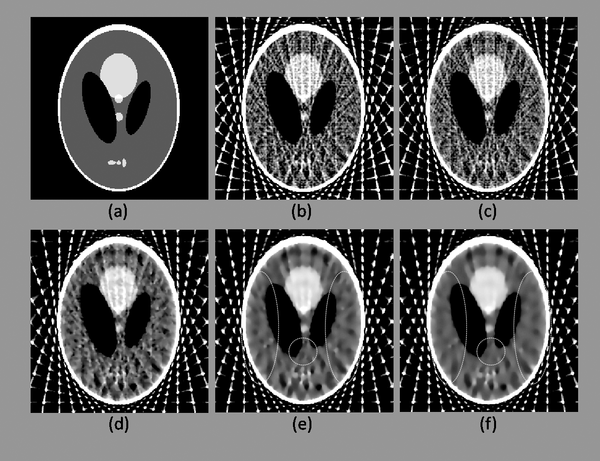

低滲漏椎體成形骨水泥灌注系統是一項用於提升椎體成形術(vertebroplasty)安全性與精密度的重要創新。其關鍵技術在於精確控制骨水泥注射過程中流量與位置,以降低水泥滲漏風險與併發症,對促進手術品質與患者康復具有深遠意義。

透過多項政府資助支持,低滲漏椎體成形骨水泥灌注系統已在安全性與效能上達到領先水準。臨床合作醫師反映,其使用後在手術定位精準、滲漏降低、術後復原加速等方面均具優勢,可望成為骨科手術的重要輔具。